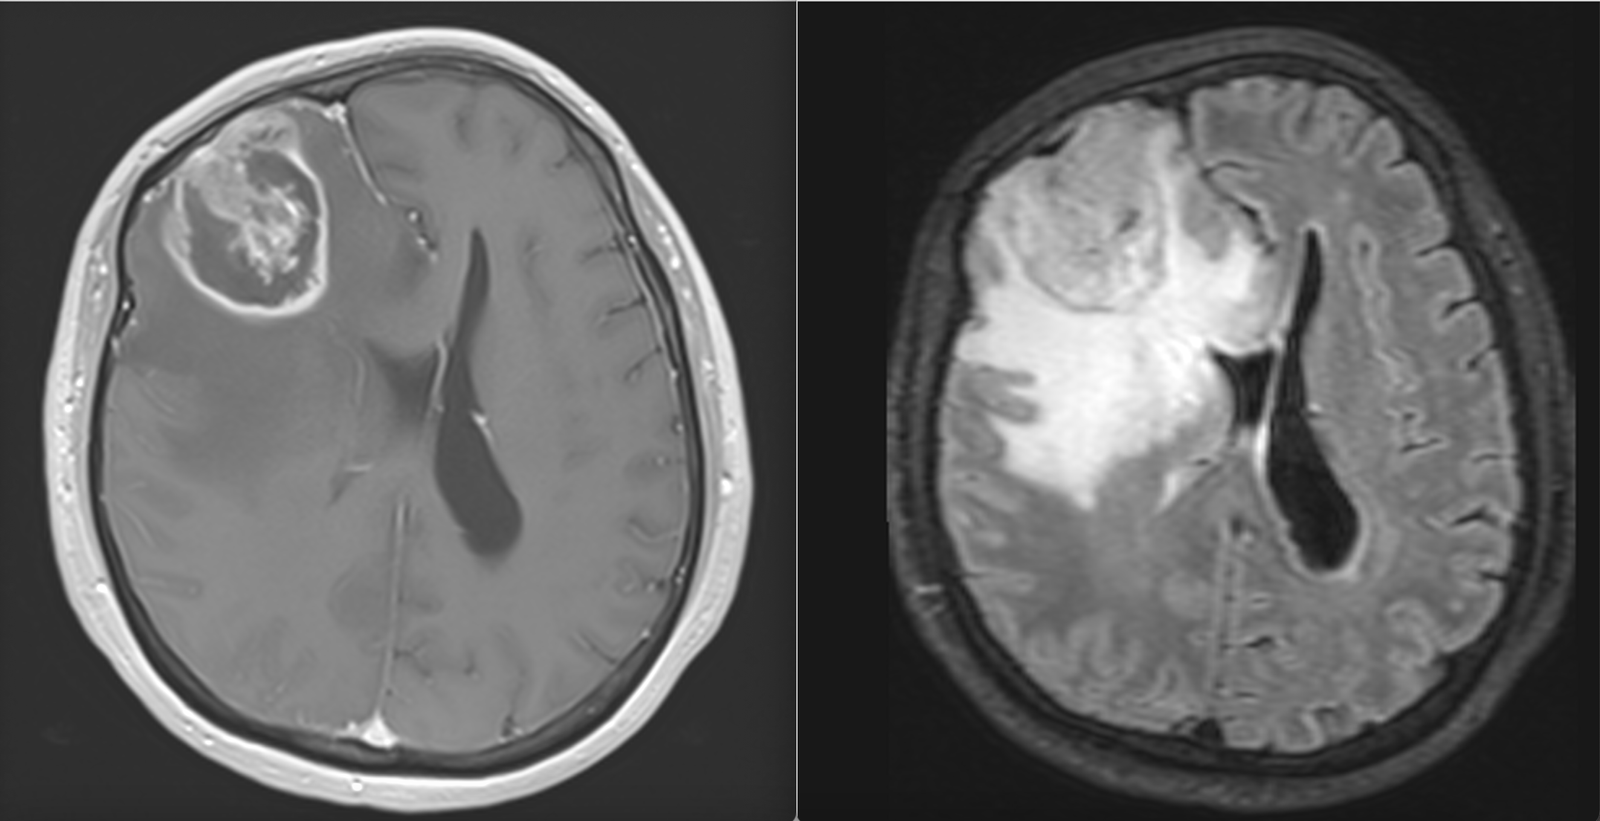

La nivel imagistic, glioblastomul apare adesea ca o leziune relativ bine delimitată, cu captare inelară de contrast și necroză centrală. Pentru ochiul neavizat, aceasta poate sugera o tumoră care ar putea fi „scoasă complet”. În realitate, ceea ce vedem pe RMN reprezintă doar componenta cea mai densă tumoral.

Imagistica – instrument esențial, dar imperfect

RMN-ul cerebral este standardul diagnostic, dar trebuie interpretat în context.

Pe lângă secvențele convenționale, tehnicile avansate aduc informații suplimentare:

- perfuzia evidențiază angiogeneza tumorală

- spectroscopia reflectă metabolismul celular

- DTI (tractografia) arată relația cu tracturile din substanța albă

Cu toate acestea, niciuna dintre aceste metode nu poate delimita complet infiltrarea microscopică. De aceea, planificarea chirurgicală și terapeutică trebuie să țină cont de această limitare.